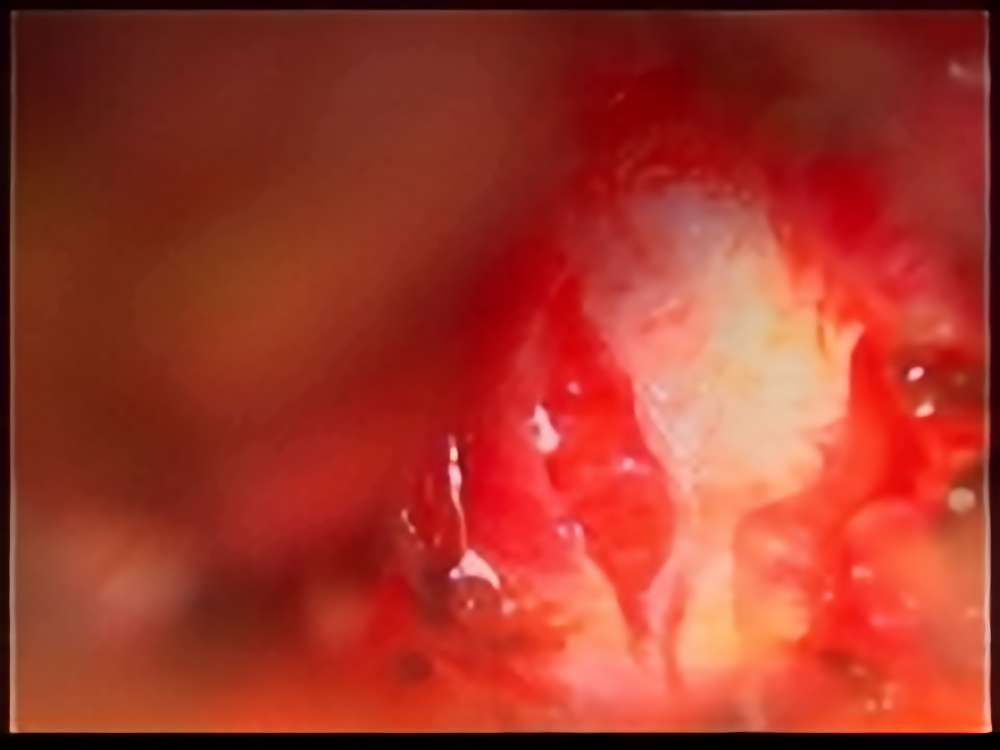

術中写真

摘出 中